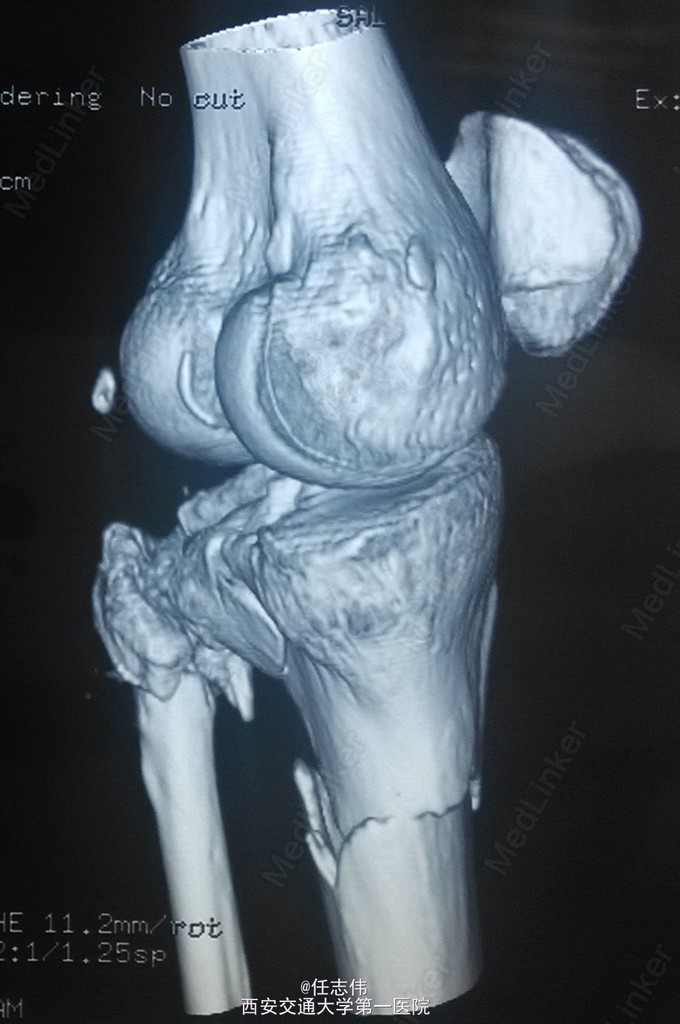

女性,66岁,摔伤致左膝部疼痛活动受限7天 7天前摔伤致左膝部疼痛伴活动受限,在当地医院行跟骨牵引、消肿对症治疗7天,已基本消肿,足部感觉、活动、血供正常。 既往有糖尿病史。

左膝关节周围肿胀,胫骨平台处压痛明显,外侧为著,膝关节活动受限。左足背动脉搏动好,踝及足趾感觉活动正常。

诊断:右胫骨平台骨折 处理:骨折切开复位内固定术。行内外侧入路钢板固定,术中行外侧平台塌陷复位,髂骨植骨内固定。另因考虑有后柱骨折,遂行后外侧切口,支撑钢板固定。术中见患者骨质疏松明显。 术后伤口愈合好,局部仍肿胀明显。

有几个问题想问问: 1.这个是胫骨平台骨折吗?还是胫骨近端骨折伴有平台骨折。 2.手术处理上有什么建议?可以不处理后侧柱吗? 3.大家在复位塌陷平台上有和经验?